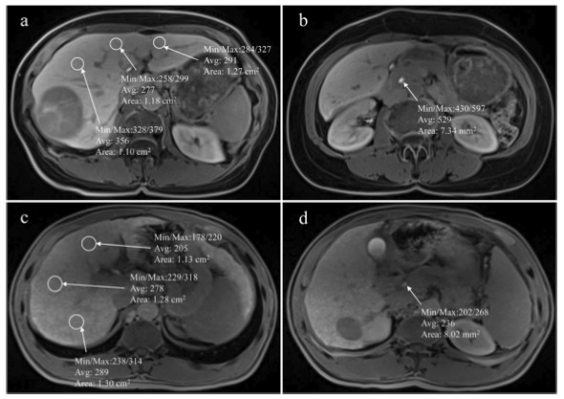

MR圖像顯示了在肝膽期測量肝臟和膽道系統的信號強度感興趣區域的位置。a和b選自一名沒有出現肝切除術后肝衰竭的患者。c和d選自一名肝切除術后出現肝衰竭的患者